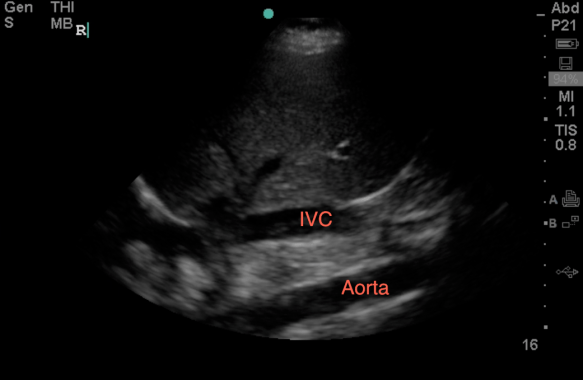

3. If you’ve done #1 and 2 above and still no go despite a valiant effort, then you can use the midaxillary approach to see a segment of the abdominal aorta in its longitudinal view (just deep to the IVC, which is just deep to the kidney and liver – so make sure to increase your depth!)

Probe position:

View: